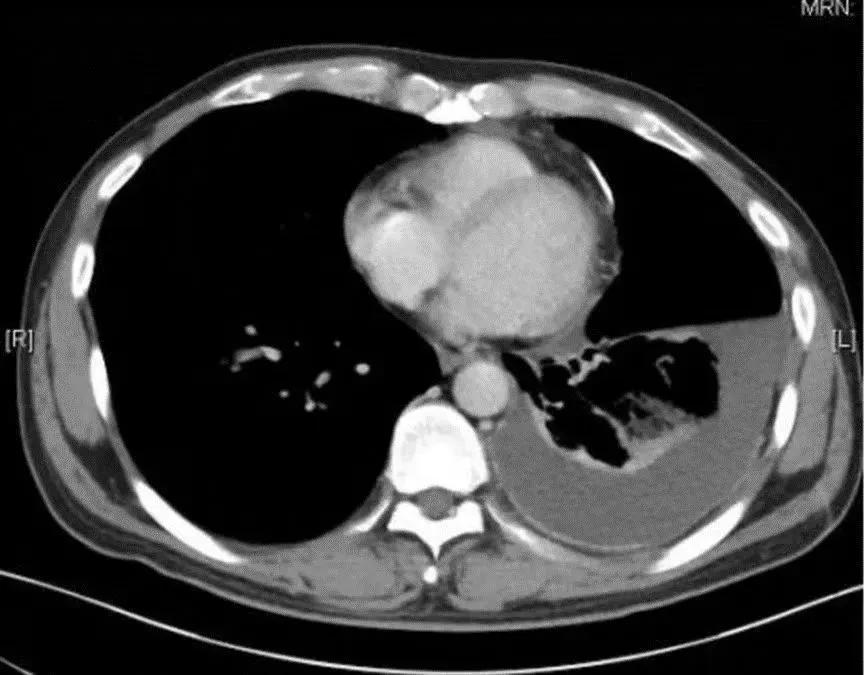

结核性胸膜炎是一种由结核杆菌引起的胸膜炎症,是肺外结核中最常见的类型之一。在结核病高发地区,结核性胸膜炎占胸腔积液疾病的一半以上。这种疾病不仅影响患者的生活质量,还可能导致严重的并发症,如胸膜增厚、包裹性积液,甚至呼吸功能减退。

随着胸膜腔内积液的增加,胸痛感可能会减轻,但随之而来的是胸闷、气促和呼吸困难。在严重情况下,患者甚至无法平卧,因为这会加剧呼吸困难。

如果出现上述症状,务必及时就医。医生会通过详细的病史询问、体格检查,以及必要的影像学检查(如胸部X线、CT扫描)和实验室检查(如血液检查、胸腔积液分析)来确诊。